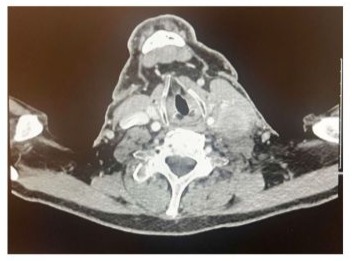

CT neck was done and declared marked interval enlargement of left sided cervical chain lymph node level 3/4a measuring 3.4 cm. It is irregular in appearance, demonstrates heterogenous enhancement and has effaced/displaced local structures. Findings highly suspicious for a metastatic lymph node (Figure 2).

Figure 2: CT neck with contrast showing marked interval